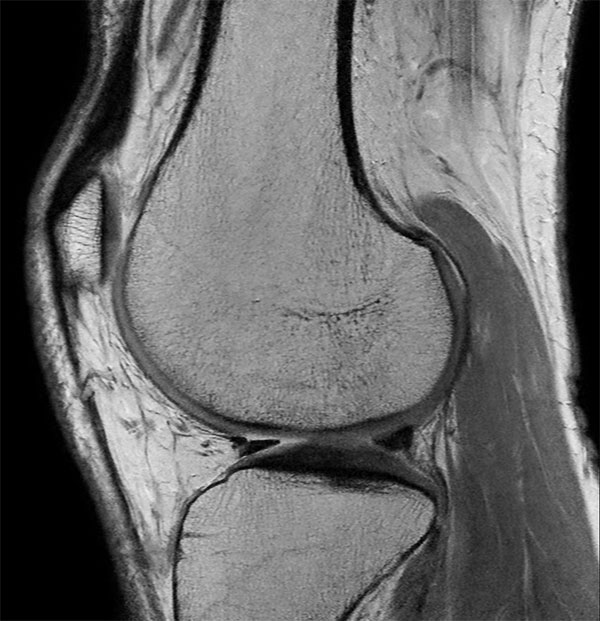

Middle aged board surfer presents with chronic knee pain. X-Ray shows no abnormalities. Follow-up MR examination requested.